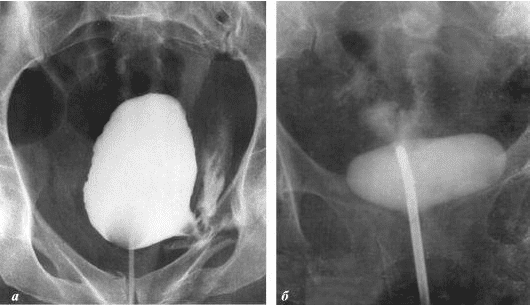

Želim da vam pokažem neke fotografije tako da sami možete vidjeti što se dešava urogenitalnom sistemu i drugim organima muškarca koji nema seksualne odnose.

Evo kako izgleda upala prostate uzrokovana stagnacijom sperme (kada se testisi ne prazne). Trajna upala dovodi do adenoma prostate, a kasnije do raka prostate (prema statistikama, 38% muškaraca umire zbog ovoga). Zbog odsustva seksa, ovo se dešava uvijek i to je razlog zašto se adenom prostate naziva "bolešću starih".